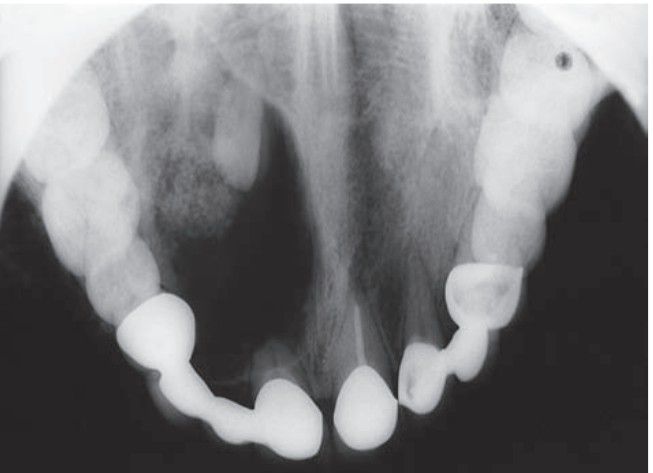

Calcifying odontogenic cyst

Calcifying odontogenic cyst of the maxilla seen in association with an impacted tooth.